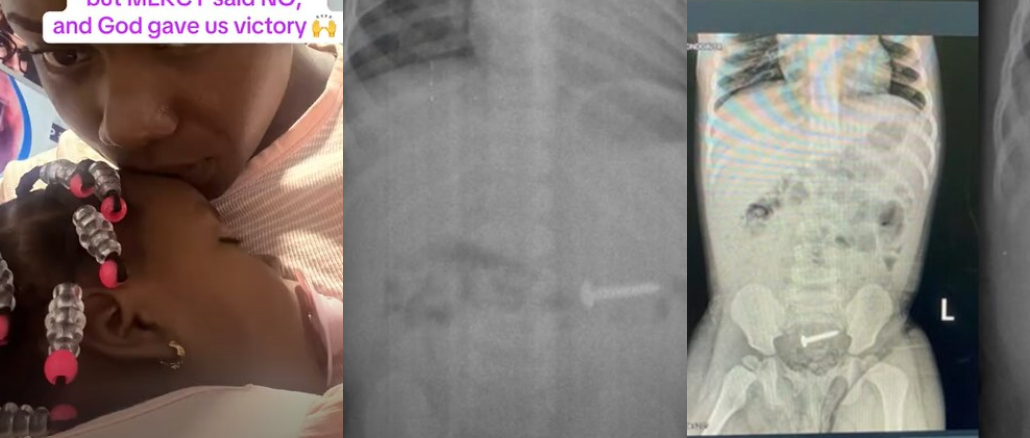

A mother tells a miracle experience involving her one-year-old daughter, who accidentally swallows a nail a week after her first birthday.

According to her, the doctor confirmed the object was trapped in the child’s system and quickly prepared the surgery for her. The news terrified the worried mother, because the idea of her little girl accepting this dangerous procedure was overwhelming.

But in a surprising twist of event, the child ended up naturally passing through her stool only after a few hours, eliminating the need for surgery.